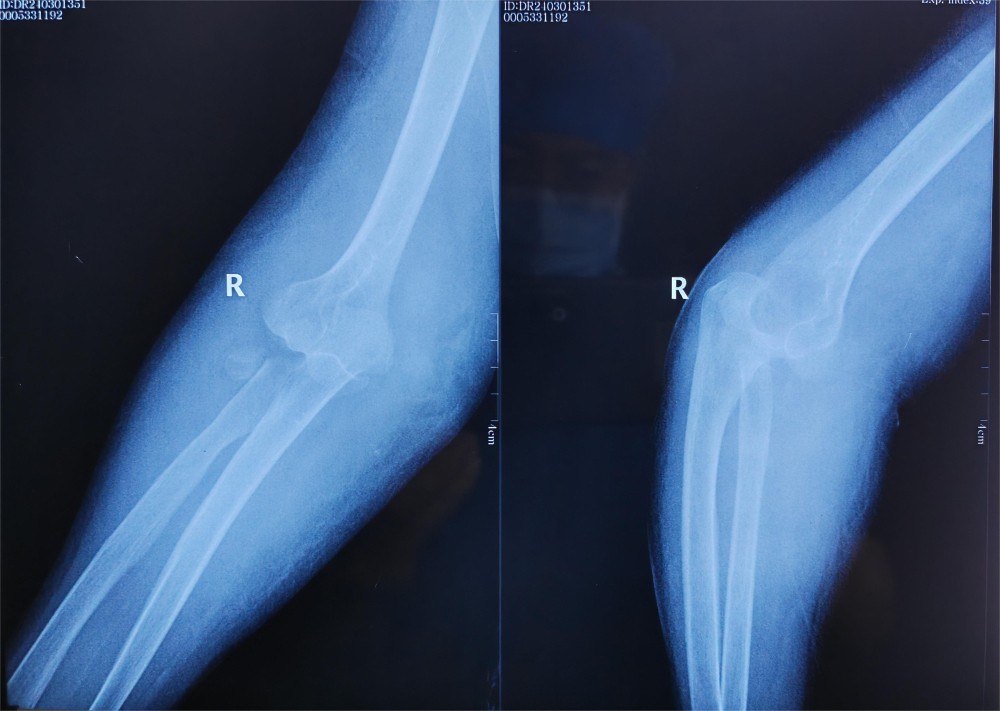

患者徐某,76岁,右肘部疼痛肿胀伴活动受限1天入院,患者于入院前1天,不慎被车从后侧撞伤,伤及右肘部,当时即感右肘部疼痛、畸形伴活动受限。受伤时患者否认头痛、头晕,胸闷、气短,恶心、呕吐等不适,被人救起后即赴某三甲医院就诊,行X光片检查显示:右肘关节脱位,右尺骨冠状突骨折,右桡骨头粉碎性骨折(肘关节恐怖三联征),给予手法复位肘关节脱位,患者为求进一步诊治赴我院门诊就诊,门诊以“1.右桡骨头粉碎性骨折2.右尺骨冠状突骨折”,收入我院创伤外科中心A区。